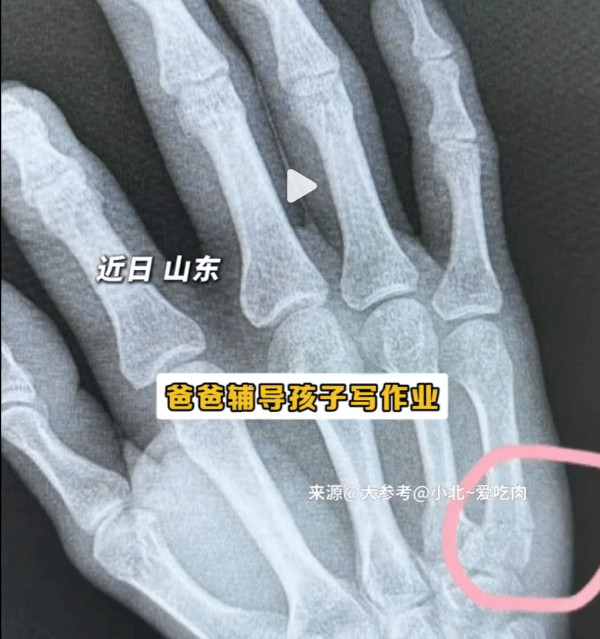

近日,山东有位父亲在辅导孩子写作业时,由于孩子半小时只写了18个字,他情绪失控拍打桌面,结果造成自己手部骨折。

这位父亲说,他舍不得打孩子,当时一时情绪激动,就把火撒到了桌子上。